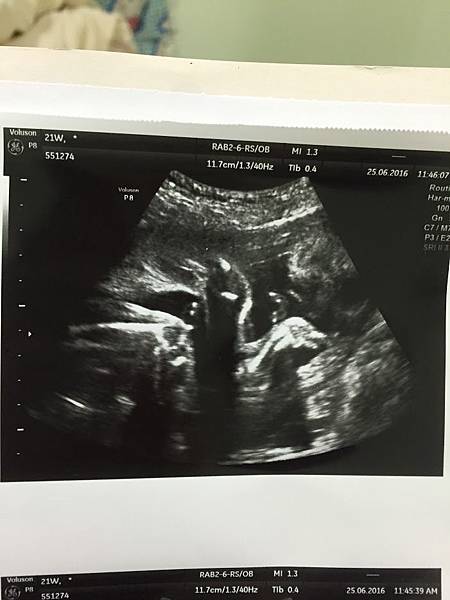

22週又五天的葉黃素 556g!

大頭側面照~可以看到鼻子嘴巴

夫君一直說她鼻子很挺有看到鼻樑不像我

哈哈哈到底對我的鼻子有什麼意見?!

最後分享幾張玄學超音波照~